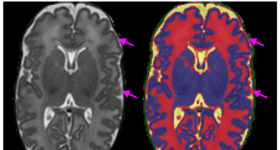

近年來,許多學者已經(jīng)提出了多種分割方法來自動描繪胎兒和新生兒腦atlas融合(deformable)模型。圍產(chǎn)期(懷孕28 周...